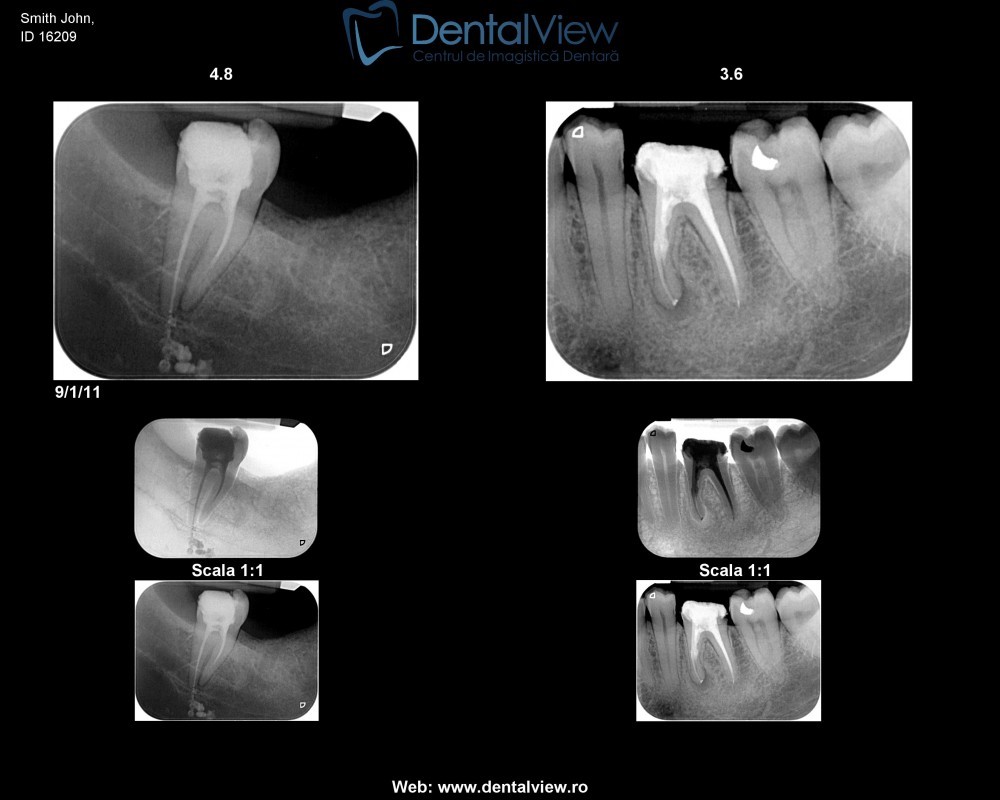

- Ca instrument de ghidare a tratamentelor endodontice;

- Numărul şi direcţia canalelor unui anumit dinte

- Poziţiile rădăcinilor unui dinte

- Retroalveolară – precisă, dar pentru doar câţiva dinţi